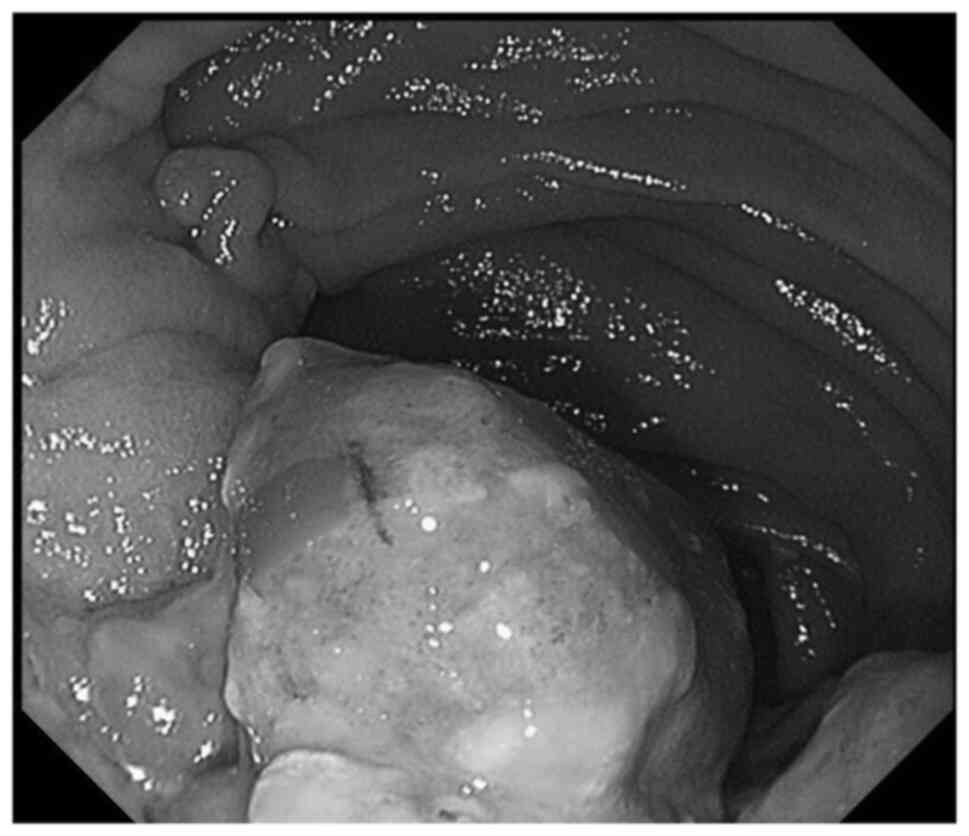

A 64-year-old man was referred to Mie University hospital on October, 2011 due to a mass on the posterior aspect of the left proximal leg. The patient had a history of a Billroth I gastroduodenostomy for a peptic ulcer. A radiograph showed an osteolytic lesion in the left proximal fibula. MRI of the left knee revealed a 6 cm mass around the proximal left fibula (Fig. 6). CT of the head, chest, abdomen, and pelvis did not demonstrate any distant metastases. An incisional biopsy was performed. Histological analysis revealed remarkably polymorphous spindle cell proliferation. Immunohistochemically, the tumor was positive for α-smooth muscle actin, desmin, and caldesmon, but negative for S100, C56, and pan CK (Table I). The aforementioned morphological and immunohistochemical findings were consistent with LMS (Figs. 7A and B, and 8). Neoadjuvant chemotherapy using doxorubicin and ifosfamide was administered. However, the lower leg could not be salvaged due to the diffuse spread to the tibia and popliteal artery. Thus, an above-knee amputation was performed. A total of 2 months after surgery, he developed multiple lung metastases. RFA was performed regularly for the lung metastases. After 1 year, the patient developed a bone metastasis of the left femur, and cryoablation and internal fixation, using a compression hip screw were performed. After 2 years, the patient presented with severe anemia without any gastrointestinal manifestations. CT revealed a protruding mass in the upper part of the stomach (Fig. 9A), and a large pericardial mass with a diameter of 56 mm. Intense FDG uptake in the stomach, left diaphragm, pericardial mass, and paraspinal muscles at the L1 and L4 levels were observed on FDG-Positron emission tomography (Fig. 9B). Cryoablation was performed for the diaphragm metastasis and paraspinal muscle metastasis. Endoscopy revealed a protruding lesion in the anastomotic site of the Billroth I, which was spreading to the jejunum (Fig. 10). The patient underwent combined resection of the stomach and transverse colon. Subsequent histochemical staining confirmed the diagnosis of gastric metastasis from LMS (Fig. 7C).

Figure 10

Gastroscopy showing a submucosal tumor in the anastomotic site of Billroth I, which was spreading to the jejunum (Case 2).